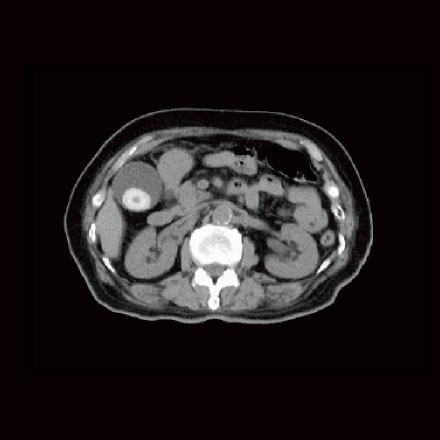

富士フイルム社の高性能64列128スライスCT「Supria Optica」を導入しています。

64断面を一度に撮影できるため、撮影時間が短く、被ばくも最小限に抑えられます。

また、AI技術を活用した画像解析によってより信頼性の高い診断を実現します。

小さな病変も捉える高精細画像

-

低被ばく量で安心負担を軽減

的確な診断をサポートAI技術搭載

スピーディーな検査検査時間が短縮

体の変化をリアルタイムで捉える